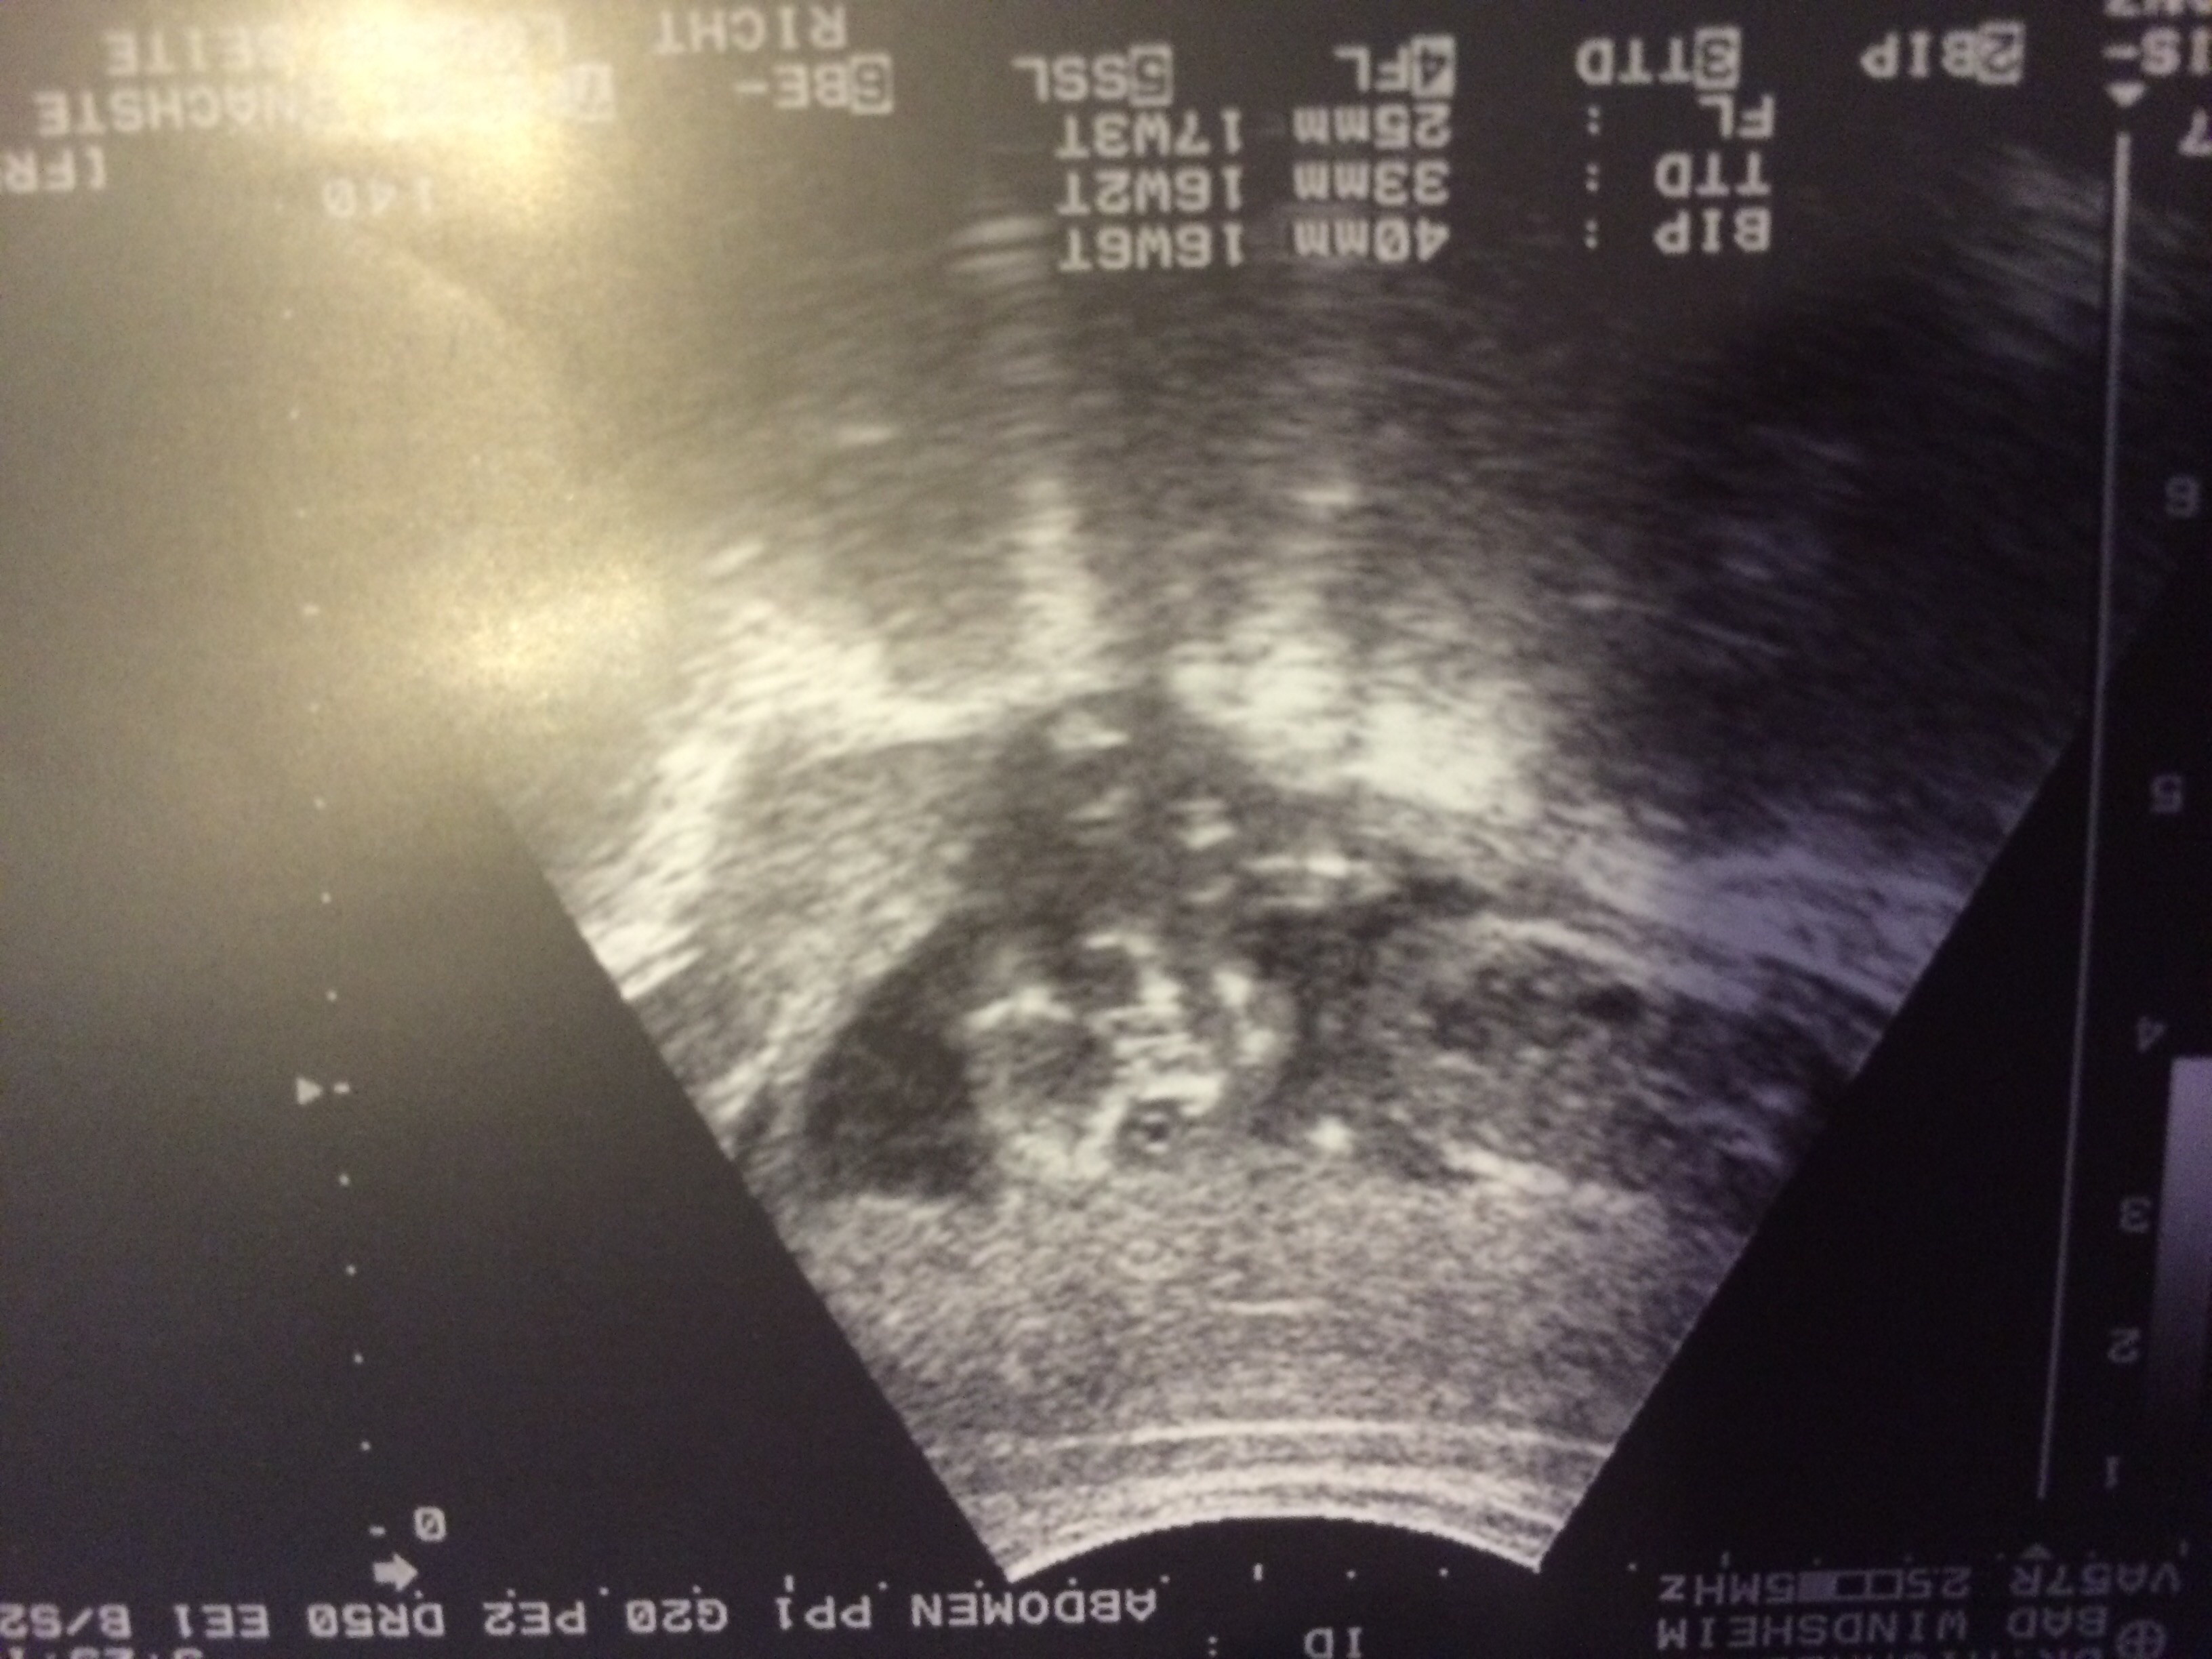

They kind of use old technology here in Germany but baby had Its legs mostly shut at my 16 week appointment. He said its leaning towards girl and he's 80% sure. There wasn't anything between the legs visibly but I guess it could have been tucked away. Looking again at the 20 week appointment. Anyone else not get a definitive answer too?got to be others in the modest baby club lol

In the meantime I got this awesomely creepy face shot of baby waving. I love it. It's so alien like haha.